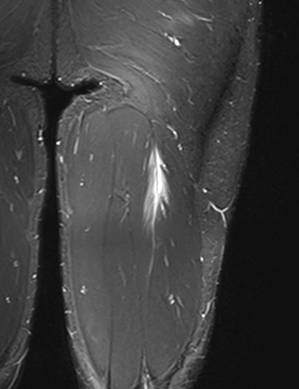

Grade 2b proximal biceps femoris